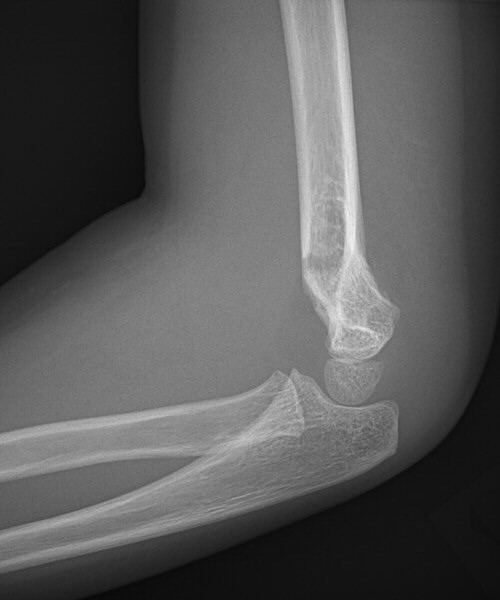

Suprakondylär humerusfraktur, Gartland 1.2, Rogers line delar capitulum radii, behandlades icke-kirurgiskt